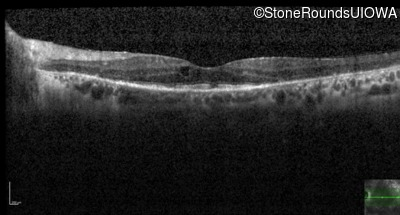

Age at visit: 60 years (Visit 3)

Age at visit: 60 years (Visit 4)

Age at visit: 62 years